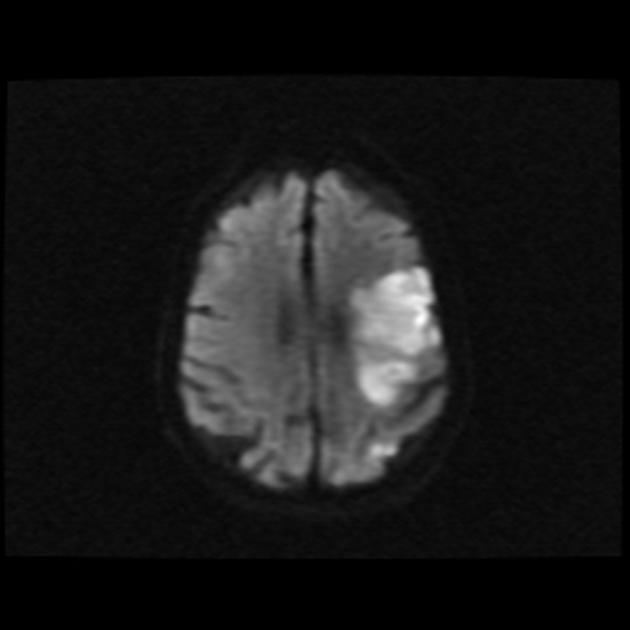

5/ DWI (Diffusion-Weighted Imaging) β Stroke & Abscess Detection

π₯οΈ Measures water diffusion in tissues

β Restricted diffusion = Bright signal (ischemic core, pus, dense tumors)

β Normal diffusion = Dark signal

π Key Uses in Neurosurgery:

β Acute Ischemic Stroke β Restricted diffusion in infarct core

β Brain abscesses β Pus has restricted diffusion

β Epidermoid cysts vs. Arachnoid cysts β Epidermoids restrict on DWI

β High-grade gliomas & metastases β Can show restricted diffusion

π¨ DWI + ADC (Apparent Diffusion Coefficient) needed for stroke timing!